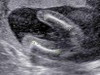

ชายรึหญิงจ๊ะ ขอแม่ๆช่วยสังเกตหน่อยย

มีความกำกวมๆ อยากรู้ว่าน้องเพศอะไร จะ20วีคละจ้า คุณหมอยังไม่ฟันธงเลยย

ก็ดูจะมีลุ้นว่าเพศชายนะคะแม่ ไม่แน่ใจเท่าไหร่